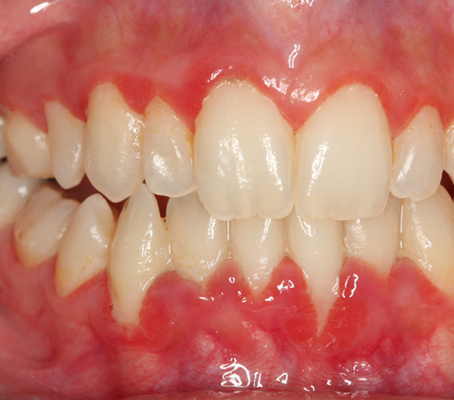

牙齦炎

牙齦炎圖片

牙齦炎和牙周炎